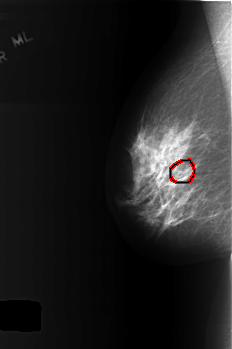

ics_version 1.0 filename C-0365-1 DATE_OF_STUDY 19 8 1996 PATIENT_AGE 52 FILM FILM_TYPE REGULAR DENSITY 2 DATE_DIGITIZED 13 10 1998 DIGITIZER LUMISYS LASER SEQUENCE LEFT_CC LINES 5536 PIXELS_PER_LINE 3744 BITS_PER_PIXEL 12 RESOLUTION 50 NON_OVERLAY LEFT_MLO LINES 5288 PIXELS_PER_LINE 3928 BITS_PER_PIXEL 12 RESOLUTION 50 NON_OVERLAY RIGHT_CC LINES 5624 PIXELS_PER_LINE 3752 BITS_PER_PIXEL 12 RESOLUTION 50 OVERLAY RIGHT_MLO LINES 5584 PIXELS_PER_LINE 3712 BITS_PER_PIXEL 12 RESOLUTION 50 OVERLAY |

FILE: C_0365_1.RIGHT_MLO.OVERLAY TOTAL_ABNORMALITIES 1 ABNORMALITY 1 LESION_TYPE CALCIFICATION TYPE AMORPHOUS DISTRIBUTION CLUSTERED ASSESSMENT 4 SUBTLETY 4 PATHOLOGY BENIGN TOTAL_OUTLINES 1 BOUNDARY |